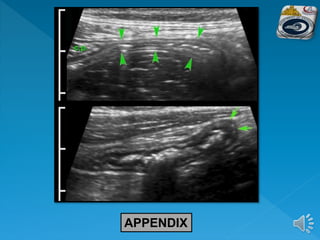

 The base of the appendix can be identified at

the deep margin of the caecum where the three

taenia coli meet

APPENDIX

Appendicular

compressibility